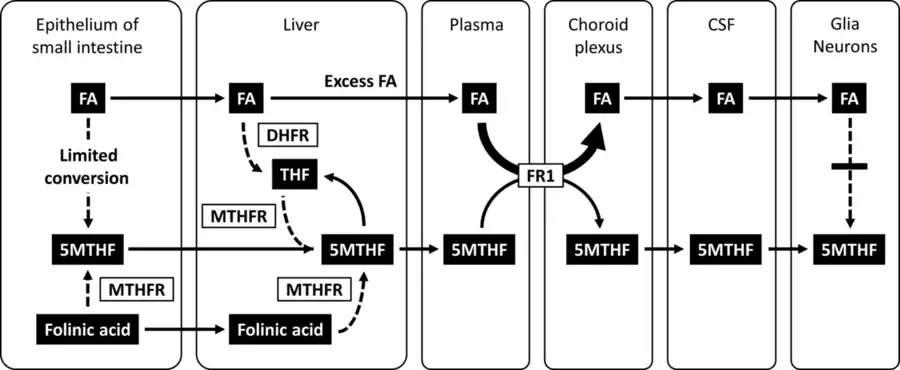

Cerebral folate deficiency is a condition in which concentrations of 5-methyltetrahydrofolate are low in the brain as measured in the cerebral spinal fluid despite being normal in the blood.[3] Symptoms typically appear at about 5 to 24 months of age.[3][2] Without treatment there may be poor muscle tone, trouble with coordination, trouble talking, and seizures.[3]

For people with the FOLR1 mutation, even when the systemic deficiency is corrected by folate, the cerebral deficiency remains, and must be treated with folinic acid. Folinic acid is a metabolically active form of folate that can be easily introduced into the folate cycle. A typical dose that is administered to children is 0.5–1 mg/kg daily, but the dose can be increased depending on the severity of symptoms and the age of the child. Over time, the treatment with folinic acid has shown to reduce a variety of symptoms of CFD. The treatment of folinic acid can lead to improvements in walking, speech, interpersonal skills and reduction in seizures.[16] Success depends on early initiation of treatment.[9] Starting the folinic acid treatment before the age of six is more advantageous for the child with CFD. If the treatment is started after the age of six, its results are not as effective.[16] Treatment requires taking folinic acid for a significant period of time.[3] Fewer than 20 people with the FOLR1 defect have been described in the medical literature.[2] Treatment with pharmacologic doses of folinic acid has also led to reversal of some symptoms in children diagnosed with cerebral folate deficiency and testing positive for autoantibodies to folate receptor alpha.[17]

5MTHF, 5-methyltetrahydrofolic acid; CSF, cerebrospinal fluid; DHFR, dihydrofolate reductase; FA, folic acid; FR1, folate receptor 1; MTHFR, methylenetetrahydrofolate reductase; THF, tetrahydrofolate"